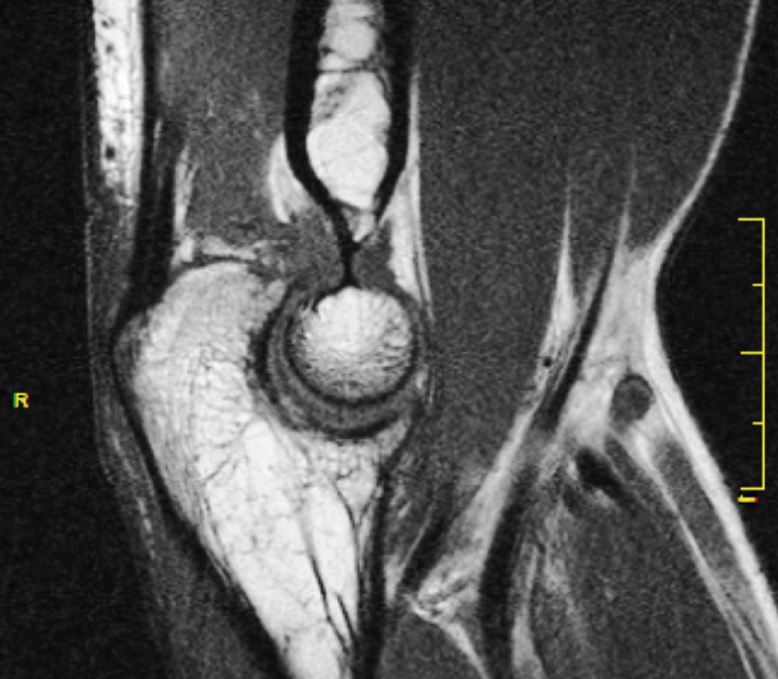

Los estudios de imagen para evaluar un codo rígido deben ser, en primer lugar, unas radiografías simples, que incluyan proyecciones anteroposterior, lateral y 2 oblicuas. Si se requieren más detalles de la superficie articular, se debe realizar una tomografía computarizada (TC) del codo con reconstrucciones tridimensionales que ayudará en la planificación quirúrgica para eliminar osteofitos y osificaciones heterotópicas (Figura 2).

Figura 2. Fibrosis articular, degeneración del cartílago y presencia de cuerpos libres no calcificados.

La resonancia magnética (RM) puede ser útil para valorar el cartílago articular, la fibrosis articular y periarticular, el estado ligamentoso y la presencia de cuerpos libres no calcificados (Figura 3).